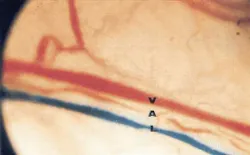

Orofacial pain. Especially in dentistry, where pain is one of the most feared expectations, pain reduction is a highly desired effect of LLLT. Achieving it requires higher doses than general stimulation, though–so pain reduction and tissue stimulation cannot be achieved at the same time. LLLT can make pain subside gradually by reducing the period of inflammation.44, 45, 46 However, the dose window for this outcome is lower than that for immediate pain reduction. LLLT stimulates opioid precursors and causes transient axonal vesicles, which reduce neural transmission (see Fig. 5).47 Trigeminal neuralgia (inflammation of the trigeminal nerve) and postherpetic neuralgia (a complication of shingles) are two indications suitable for LLLT.48, 49, 50, 51 This therapy is not likely to cure a trigeminal neuralgia, but it will facilitate a reduction of intake of the prescription drug Carbamazepine.